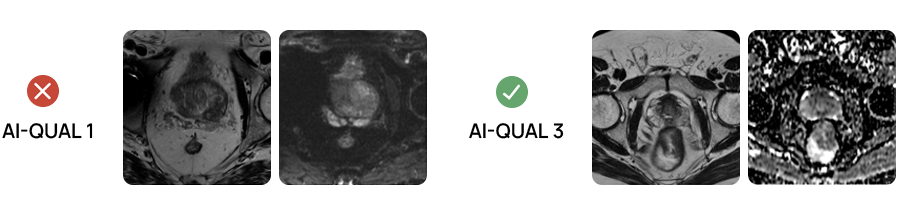

AI-QUAL™: Automated Prostate Image Quality Assessment

Quibim’s AI-QUAL™ automates the assessment of prostate MRI image quality based on the PI-QUALv2 guidelines. This tool streamlines workflows and supports diagnostic confidence.

Key benefits of AI-QUAL include:

- Automated Quality Scoring: Eliminates manual checks, saving time and reducing subjectivity.

- Standardized Reporting: Delivers consistent quality score based on PI-QUAL v2 guidelines.

- Artifact Detection: Identifies key image-degrading factors such as rectal gas distortion and metal artifacts.

- Diagnostic Confidence: Ensures radiologists work with the highest quality images.

- Seamless Integration: Designed to fit effortlessly into existing radiology workflows.